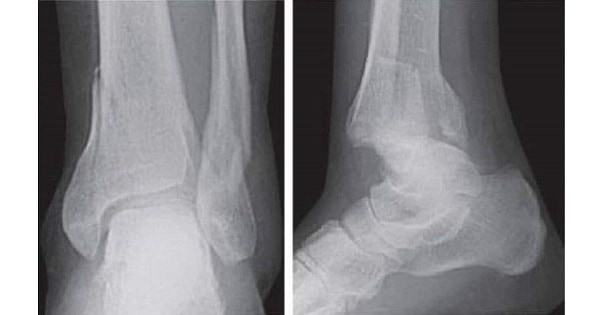

A patient presented with Ankle pain.X ray showed the following features.Identify this condition:

Ans:C.)Pott’s Fracture

Pott’s Fracture

- Fracture of the lower end of the fibula and medial malleolus of the tibia with rupture of the internal lateral ligament of the ankle, caused by outward and backward displacement of the leg while the foot is fixed.

- Pott’s fracture (also: Bimalleolar fractures) involve at least 2 elements of the ankle ring. These fractures should be considered unstable and require urgent orthopedic attention.

Image shows:

- The Anterior-Posterior (AP) image shows fractures of both the lateral malleolus and medial malleolus.

- The lateral image shows an additional fracture line passing in the coronal plane to the articular surface of the tibia

- The posterior corner of the tibia is also known as the ‘posterior malleolus’.

Cotton Fracture(Trimalleolar Fracture)

- A trimalleolar fracture is a fracture of the ankle that involves the lateral malleolus, the medial malleolus, and the distal posterior aspect of the tibia, which can be termed the posterior malleolus.

- Surgical repair using open reduction and internal fixation is generally required